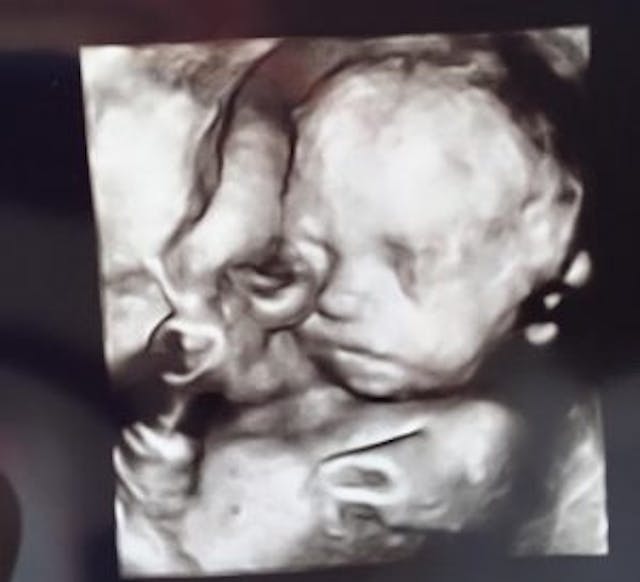

In November of 2015, Greg and Heather Puruleski learned that their fourth child, Jonah, had Trisomy 18, also known as Edward’s syndrome. Parents of children diagnosed with this condition prenatally are often advised to abort their baby, but this couple refused and worked to give their son every chance possible.

Baby Jonah, while still in the womb, was also diagnosed with a heart condition that would require surgery: a surgery the local hospital – Helen DeVos Children’s Hospital – refused to provide. So the couple turned to the University of Michigan, which agreed to perform the surgery.

On April 26, 2016, Jonah was born via c-section at the University of Michigan, weighing just 3 pounds, 12 ounces. Although doctors predicted he might not survive birth, or live long after birth, his mother wrote on Facebook that he was doing well.